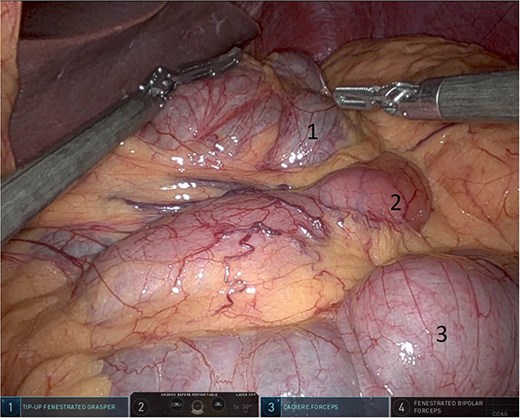

Upon entering the abdominal cavity, dilated bowel loops were observed (Fig. 2), and a significant portion of the colon was found herniated through the foramen of Winslow (Fig. 3). The herniated colon was covered by the pars flaccida (Fig. 4) (Video S1). Careful dissection was performed anterior to the hepatoduodenal ligament (Fig. 5). The gall bladder was retracted to the patient's right upper quadrant, which allowed for the retraction of the foramen of Winslow (Fig. 6) (Video S1). After carefully placing the tip of the instrument posterior to the portal vein and gently elevating it, the herniated colon was successfully reduced (Fig. 7) (Video S1).

Pars flaccida covering the herniated bowel (1: pars flaccida over the herniated bowel, 2: the stomach, 3: transverse colon).